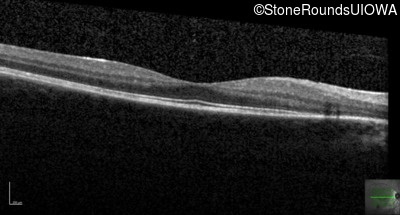

Age at visit: 14 years

Age at visit: 15 years

Age at visit: 16 years

Age at visit: 18 years

Age at visit: 18 years (Visit 2)

Age at visit: 19 years

Age at visit: 20 years

Age at visit: 22 years